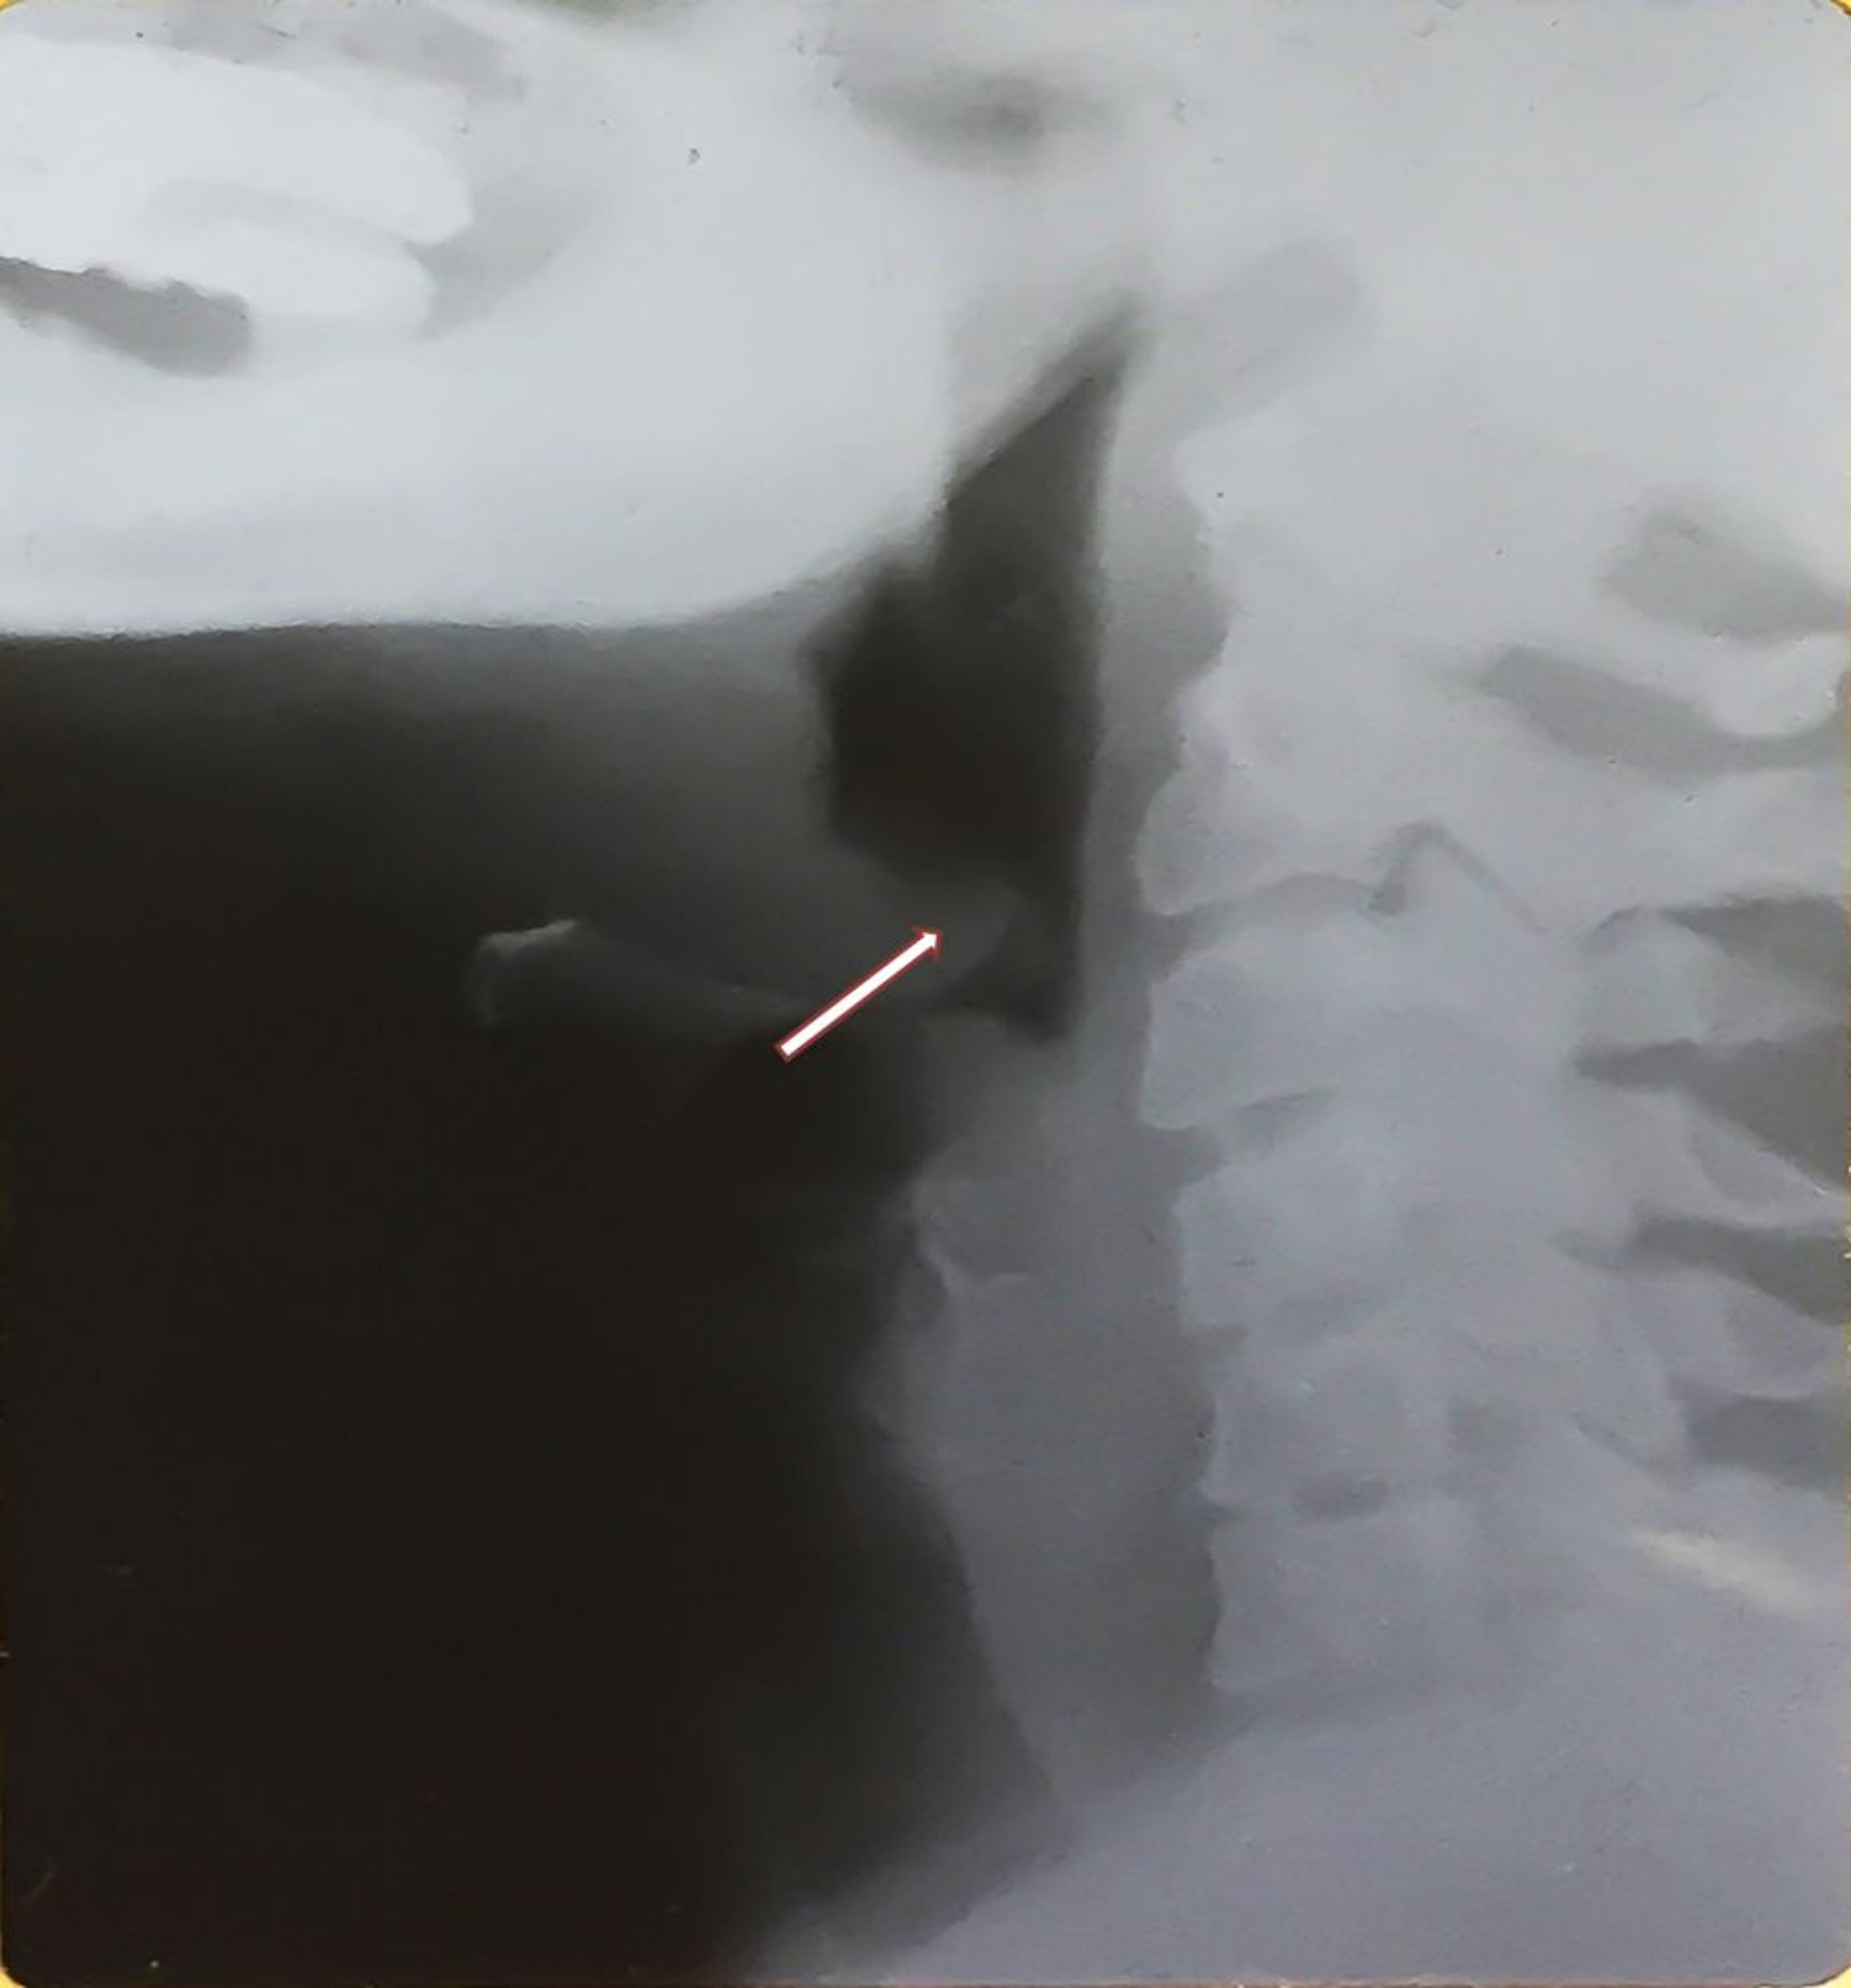

This x-ray shows the enlarged epiglottis (thumb sign—see arrow) characteristic of epiglottitis and distention of the hypopharynx. Note the posteriorly displaced, thickened epiglottis.

Image provided by Clarence T. Sasaki, MD.